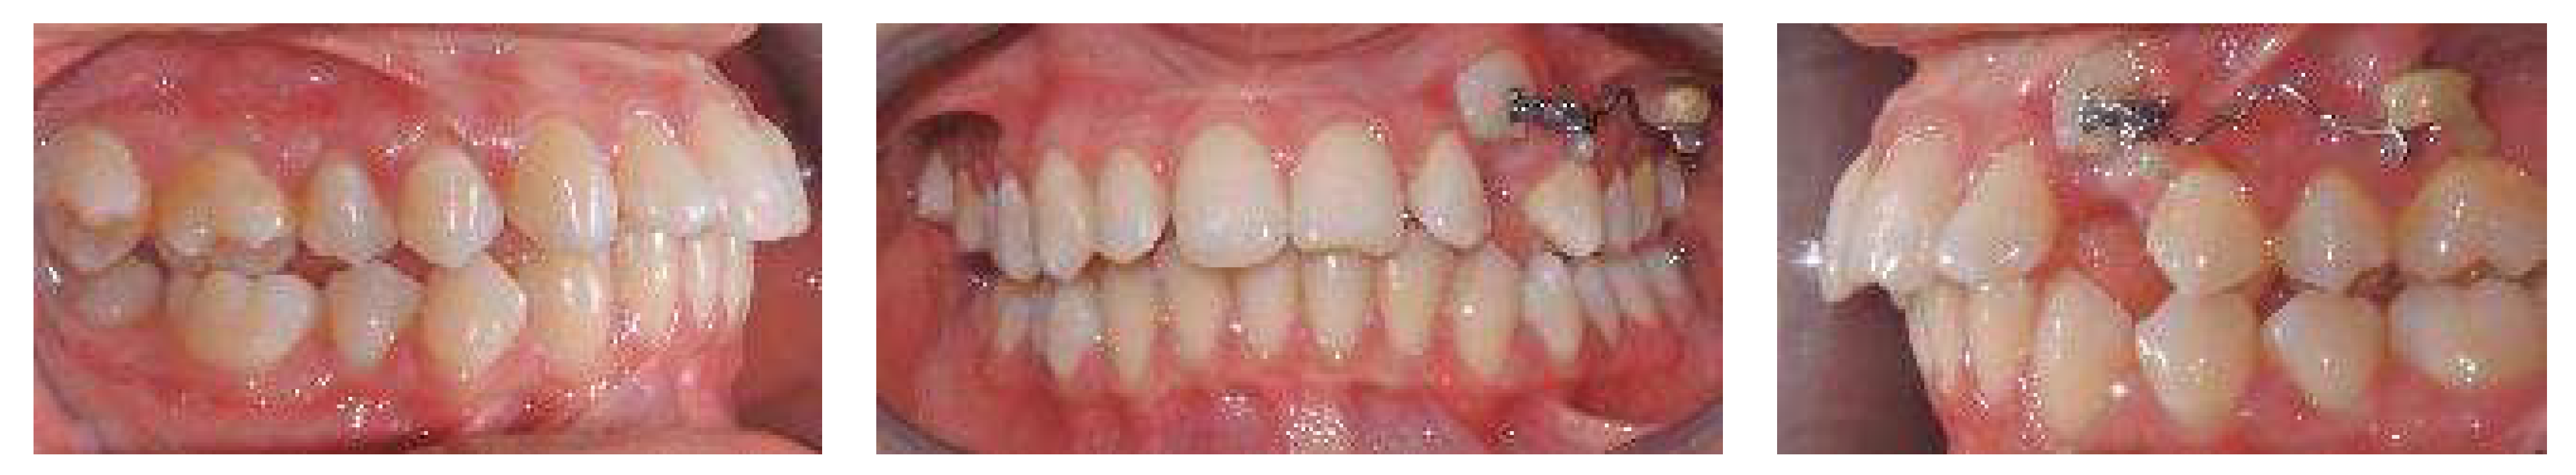

A 17-year-old female patient came for an observation in good general and oral health without any significant pathologies.

The chief complaint of the patient was the absence of a permanent maxillary canine. Her face, from a frontal view, appeared well-proportioned in the three-thirds with facial symmetry.

From a lateral view, the profile appeared straight and a normal nasolabial angle, labiomental sulcus, and lip competence was represented. The initial records were collected and X-rays were taken (Figure 1).

A 17-year-old female with dentoskeletal Class I with an impacted upper right canine before treatment.

Intraorally, the patient had Class I molar and canine relation on both sides, along with normal overbite, overjet, and the retention of the deciduous canine.

The cephalometric analysis showed a skeletal Class I (ANPg +1.7°) with a good proportion of the maxillaries (SNA 84°; SNB 82.3°) in a normo-divergent vertical pattern (SN^Go-Gn = 32.8°) and a good inclination of the upper and lower teeth, respectively (I/ANS-PNS 116.2°; i/GoGn 91.6°) (Table 1).